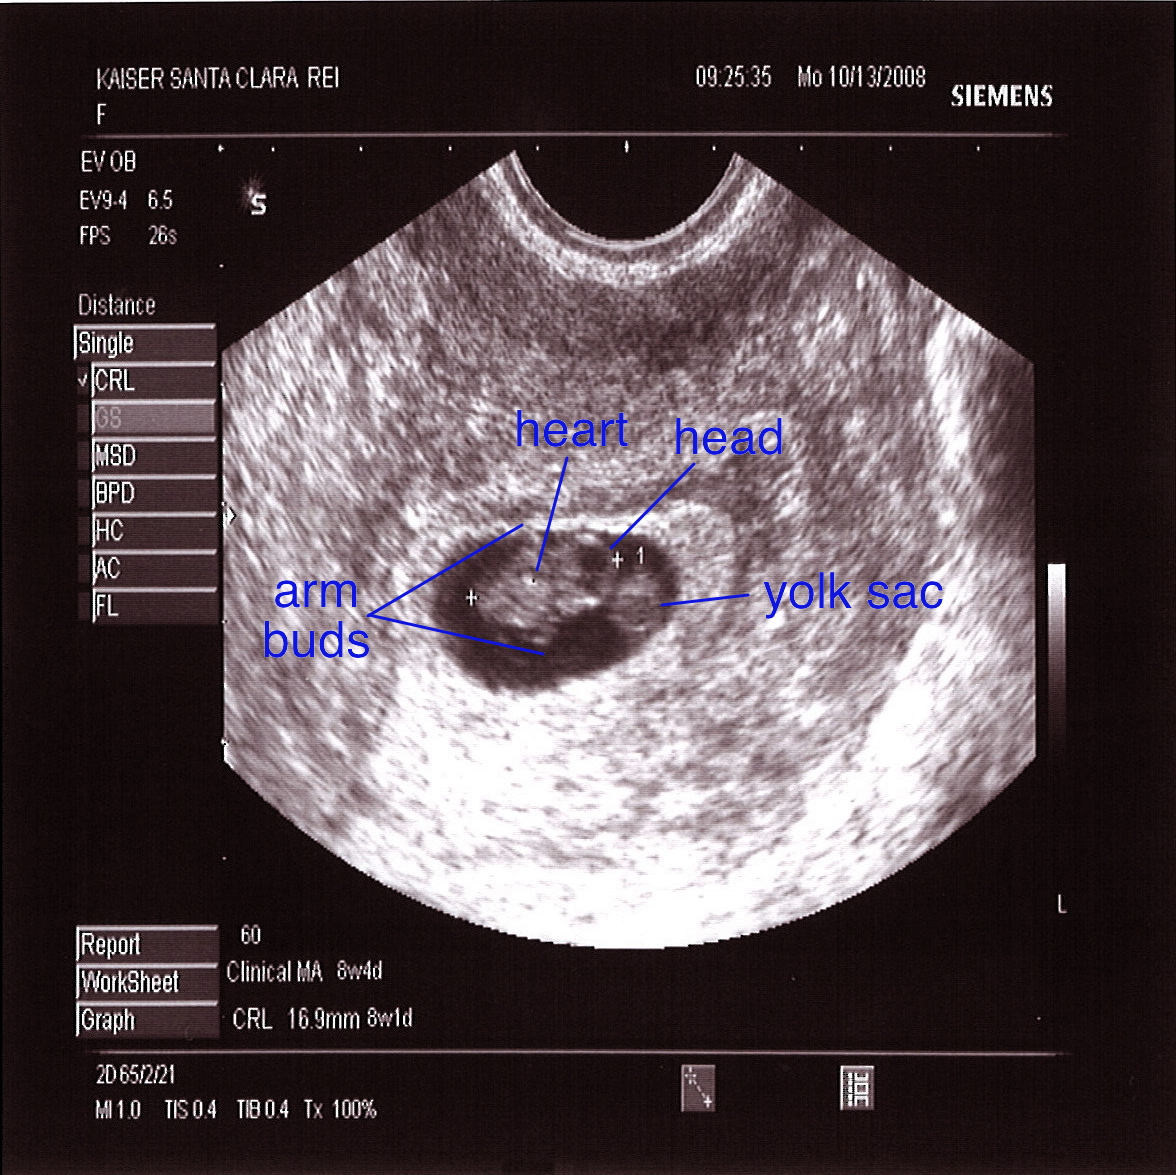

Ultrasound scans at 8 weeks pics.

The Pregnancy Diaries: I’m 8 weeks pregnant! – Life Education Council